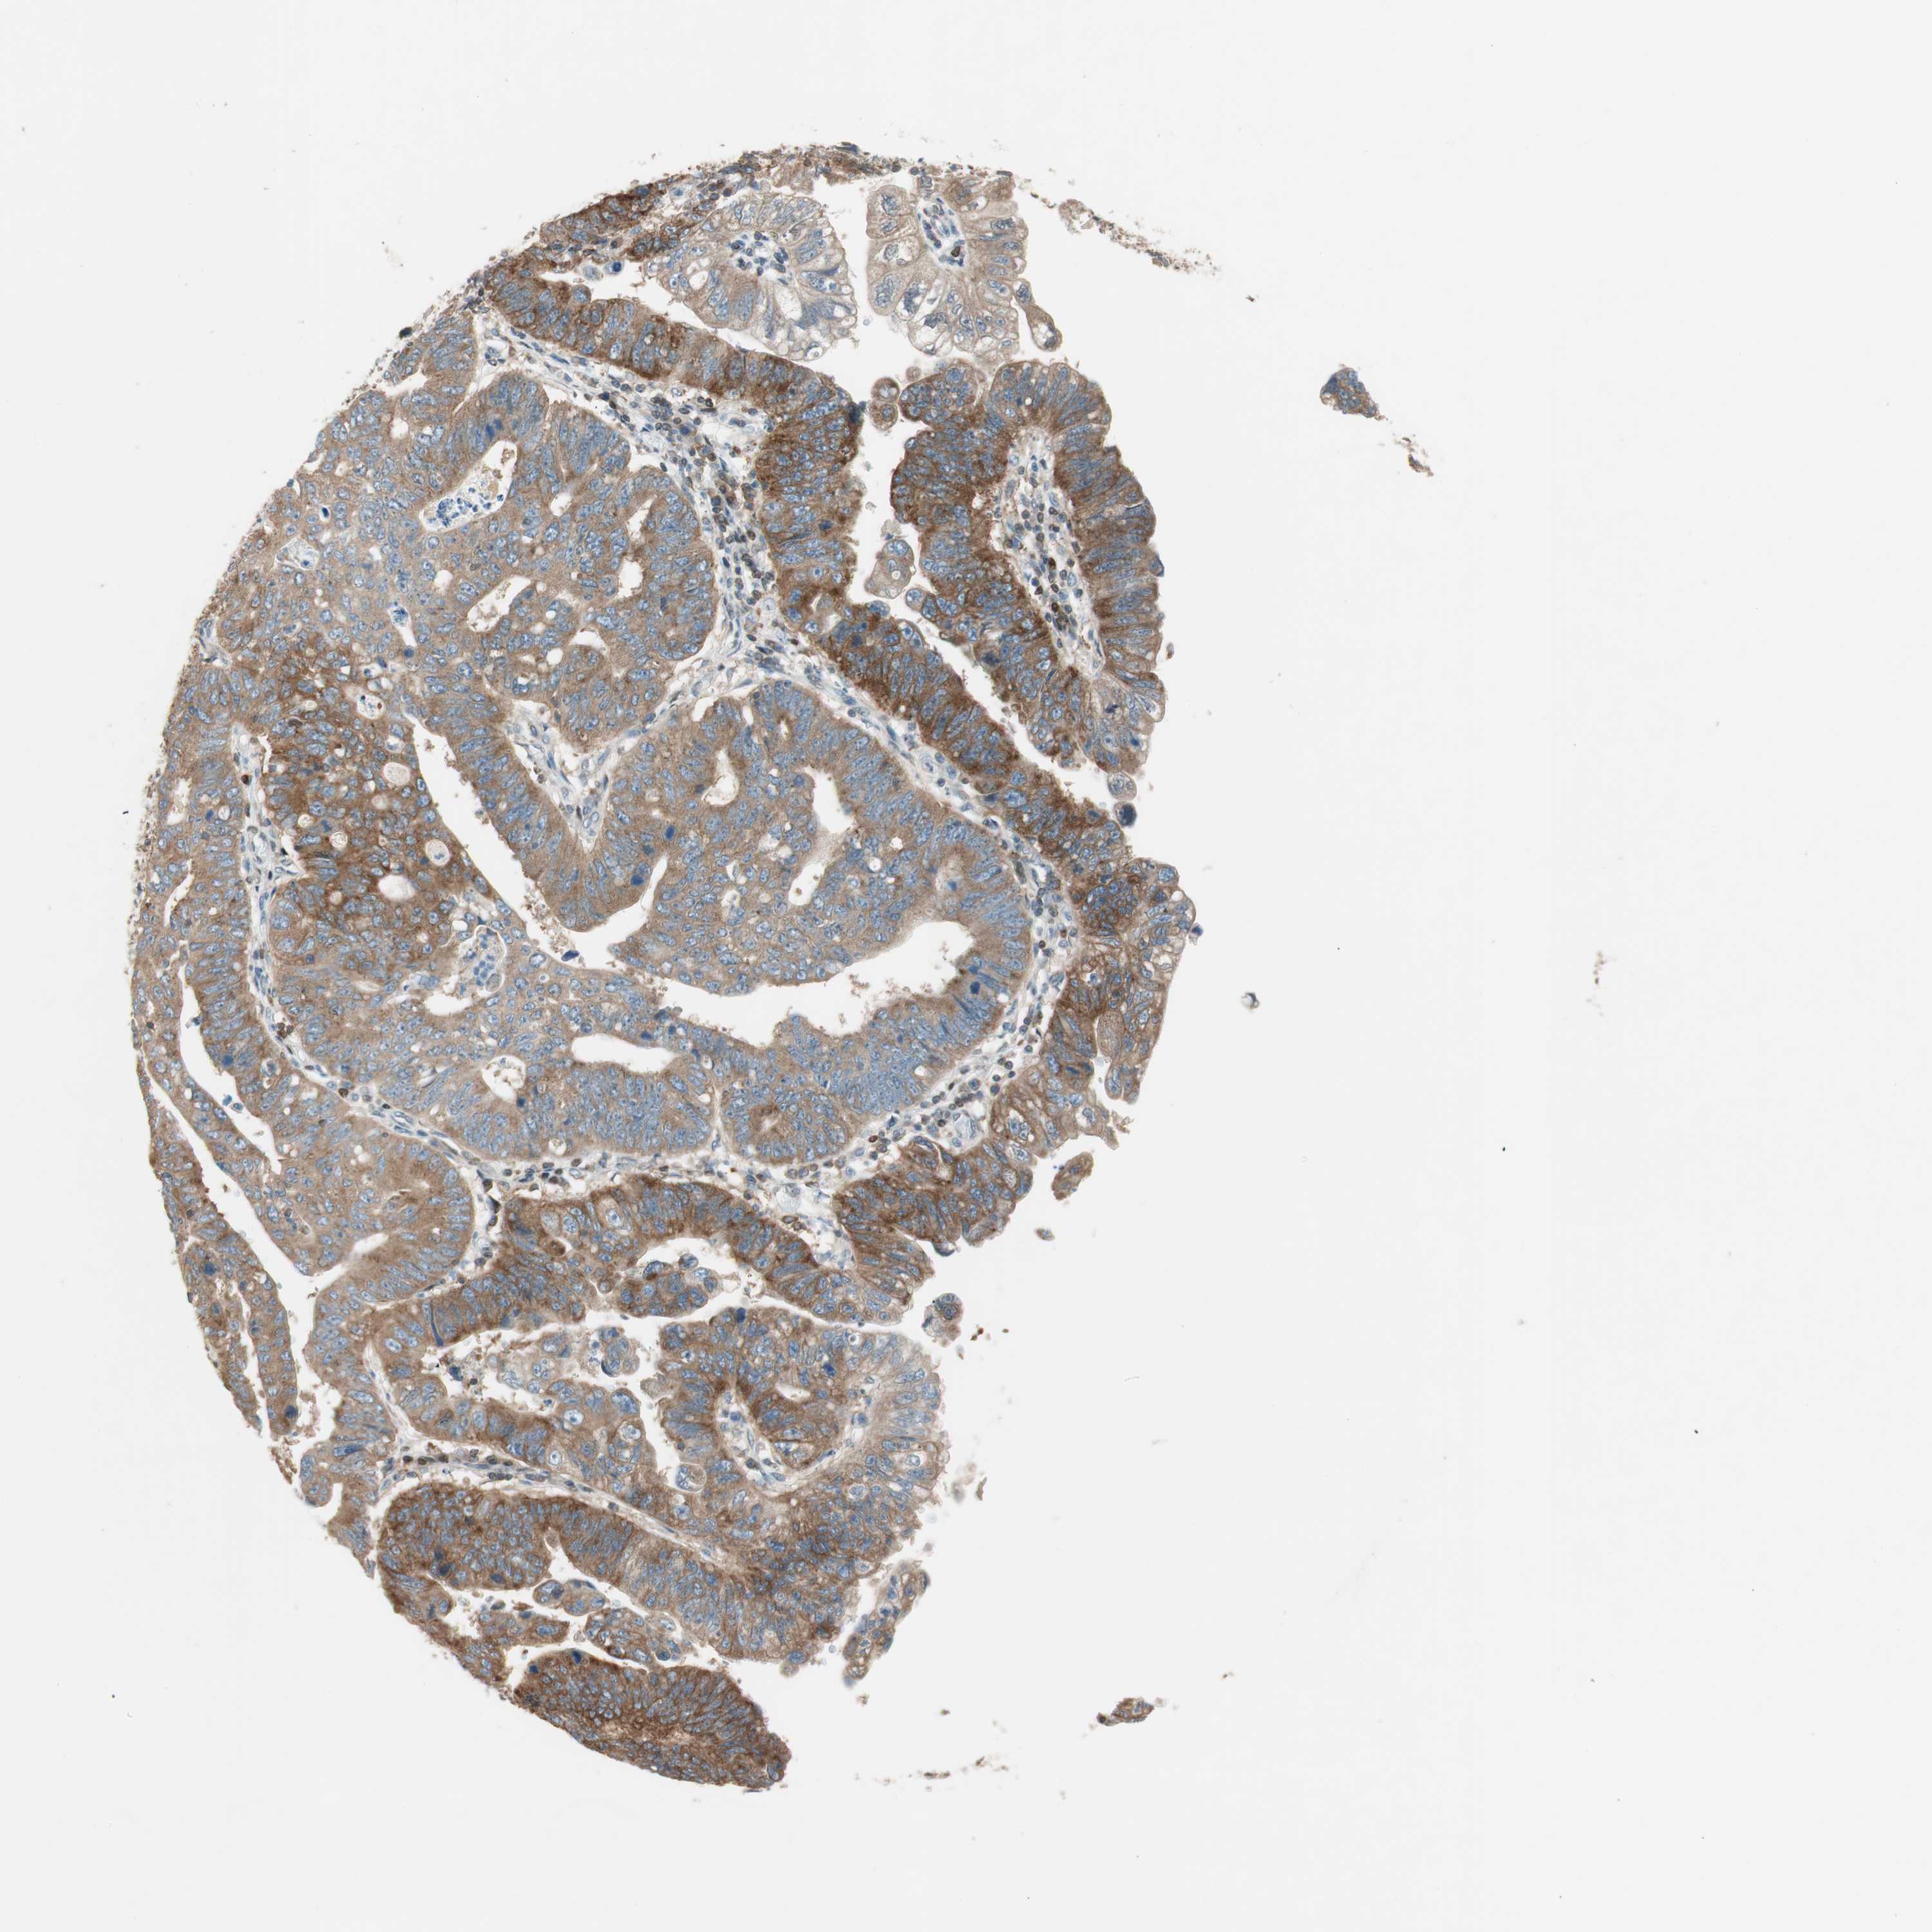

STOMACH CANCER - Protein expressioni

A mouse-over function shows sample information and annotation data. Click on an image to view it in a full screen mode. Samples can be filtered based on level of antibody staining by selecting one or several of the following categories: high, medium, low and not detected. The assay and annotation is described here.

Note that samples used for immunohistochemistry by the Human Protein Atlas do not correspond to samples in the TCGA dataset.

Antibody stainingi

Antibody staining in the annotated cell types in the current human tissue is reported as not detected, low, medium, or high, based on conventional immunohistochemistry profiling in selected tissues. This score is based on the combination of the staining intensity and fraction of stained cells.

Each image is clickable and will lead to virtual microscopy that enables deeper exploration of all samples and also displays staining intensity scores, fraction scores and subcellular localization as well as patient and tissue information for each sample.

Antibody HPA003894

Antibody HPA005437

Antibody CAB001945

Staining

High

Medium

Low

Not detected

Intensity

Strong

Moderate

Weak

Negative

Quantity

>75%

75%-25%

<25%

None

Location

Nuclear

Cytoplasmic/membranous

Cytoplasmic/membranous,nuclear

Adenocarcinoma, NOS

Adenocarcinoma, High grade